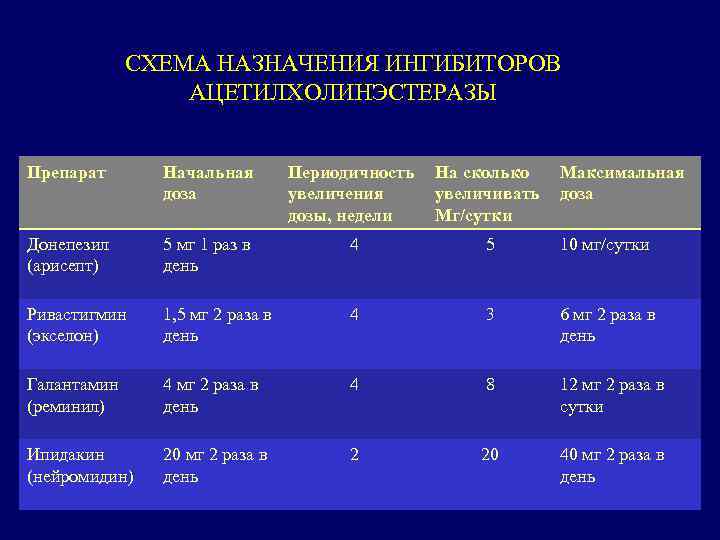

СХЕМА НАЗНАЧЕНИЯ ИНГИБИТОРОВ АЦЕТИЛХОЛИНЭСТЕРАЗЫ Препарат Начальная доза Периодичность увеличения дозы, недели На сколько увеличивать Мг/сутки Максимальная доза Донепезил (арисепт) 5 мг 1 раз в день 4 5 10 мг/сутки Ривастигмин (экселон) 1, 5 мг 2 раза в день 4 3 6 мг 2 раза в день Галантамин (реминил) 4 мг 2 раза в день 4 8 12 мг 2 раза в сутки Ипидакин (нейромидин) 20 мг 2 раза в день 2 20 40 мг 2 раза в день